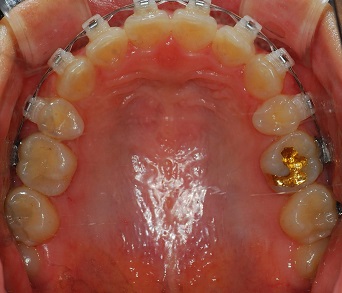

치과쌤이 치아를 쭉보시고 와이어를 얇은것으로 바꿔주셧어요.

드뎌드뎌 치아교정 마무리 작업에 슬슬 들어가는군용!

발치 공간은 다 닫혓어요. ^__________^

(상악사진)

측면에서도 치아 사이에 구멍은 보이지 않아요!